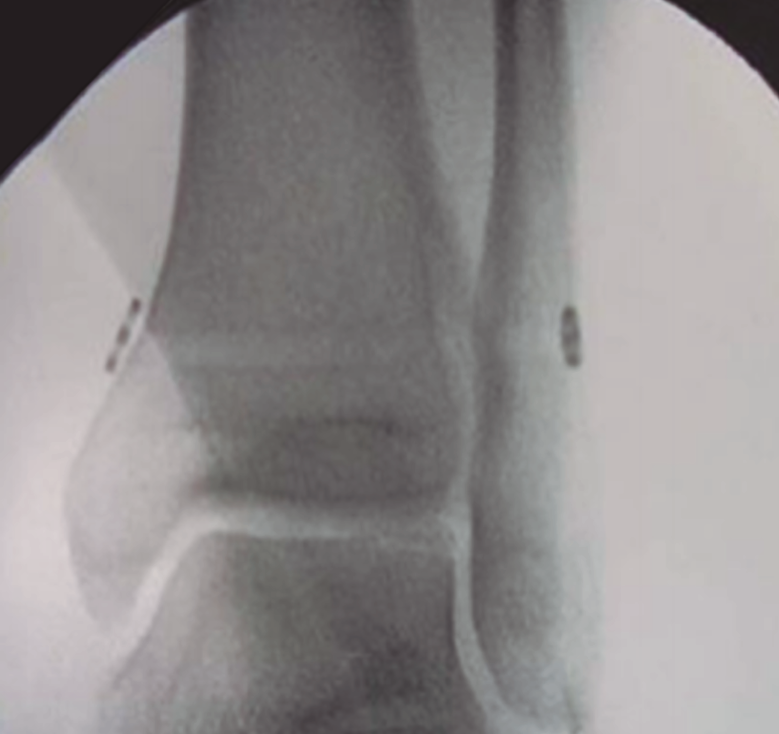

El método de tratamiento convencional suele ser la fijación de la sindesmosis con un tornillo de cortical a través del peroné situado a 2 o 3 cm por encima de la línea articular para evitar lesiones de los ligamentos y angulado de 20 a 30° anterior y medial(14,15). Se ha demostrado que 2 tornillos ofrecen mayor resistencia que un tornillo simple y que los tornillos de 4,5 mm son más resistentes que los de 3,5 mm. Más de 2 tornillos o de mayor diámetro no son aconsejables, ya que pueden provocar una fractura del peroné(2). Según lo publicado hasta ahora, no hay diferencias significativas entre el paso de 3 o 4 corticales. La carga completa no se recomienda hasta al menos 2 meses, una vez retirado el tornillo, para evitar roturas o síntomas dolorosos en la articulación del tobillo. Si bien está en discusión, ya que no parece haber diferencia significativa en el resultado funcional entre los pacientes que se sometieron a la extracción de rutina del tornillo transin­desmal y los pacientes en los que el tornillo solo se extrajo en caso de implantes sintomáticos(16) (Figura 3).

figura3.png

Figura 3. Fijación rígida con tornillos.